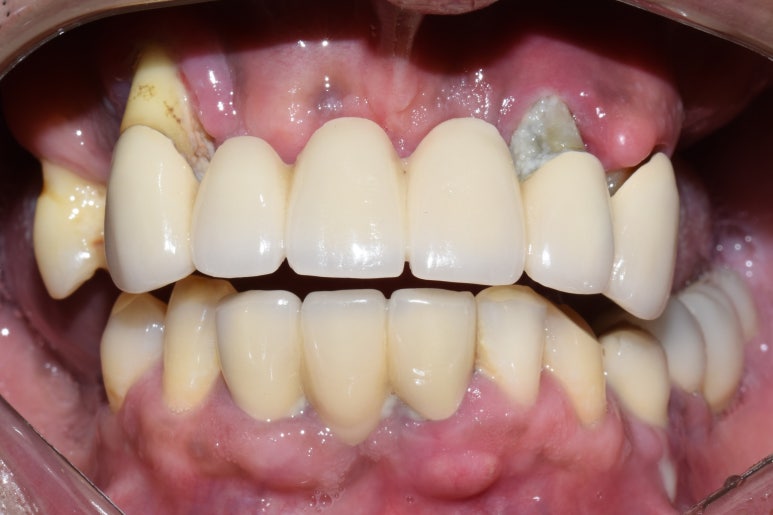

아래는 전후 비교사진입니다.

전 & 후

치료 후

위의 사진처럼 이제 환하게 웃을 수도 있고, 어금니로 음식도 잘 드실 수 있어서

5kg나 쪘다고 이번 체크 때 말씀해 주셨어요 ^^

환자분이 만족해하시니 저희도 행복해요!